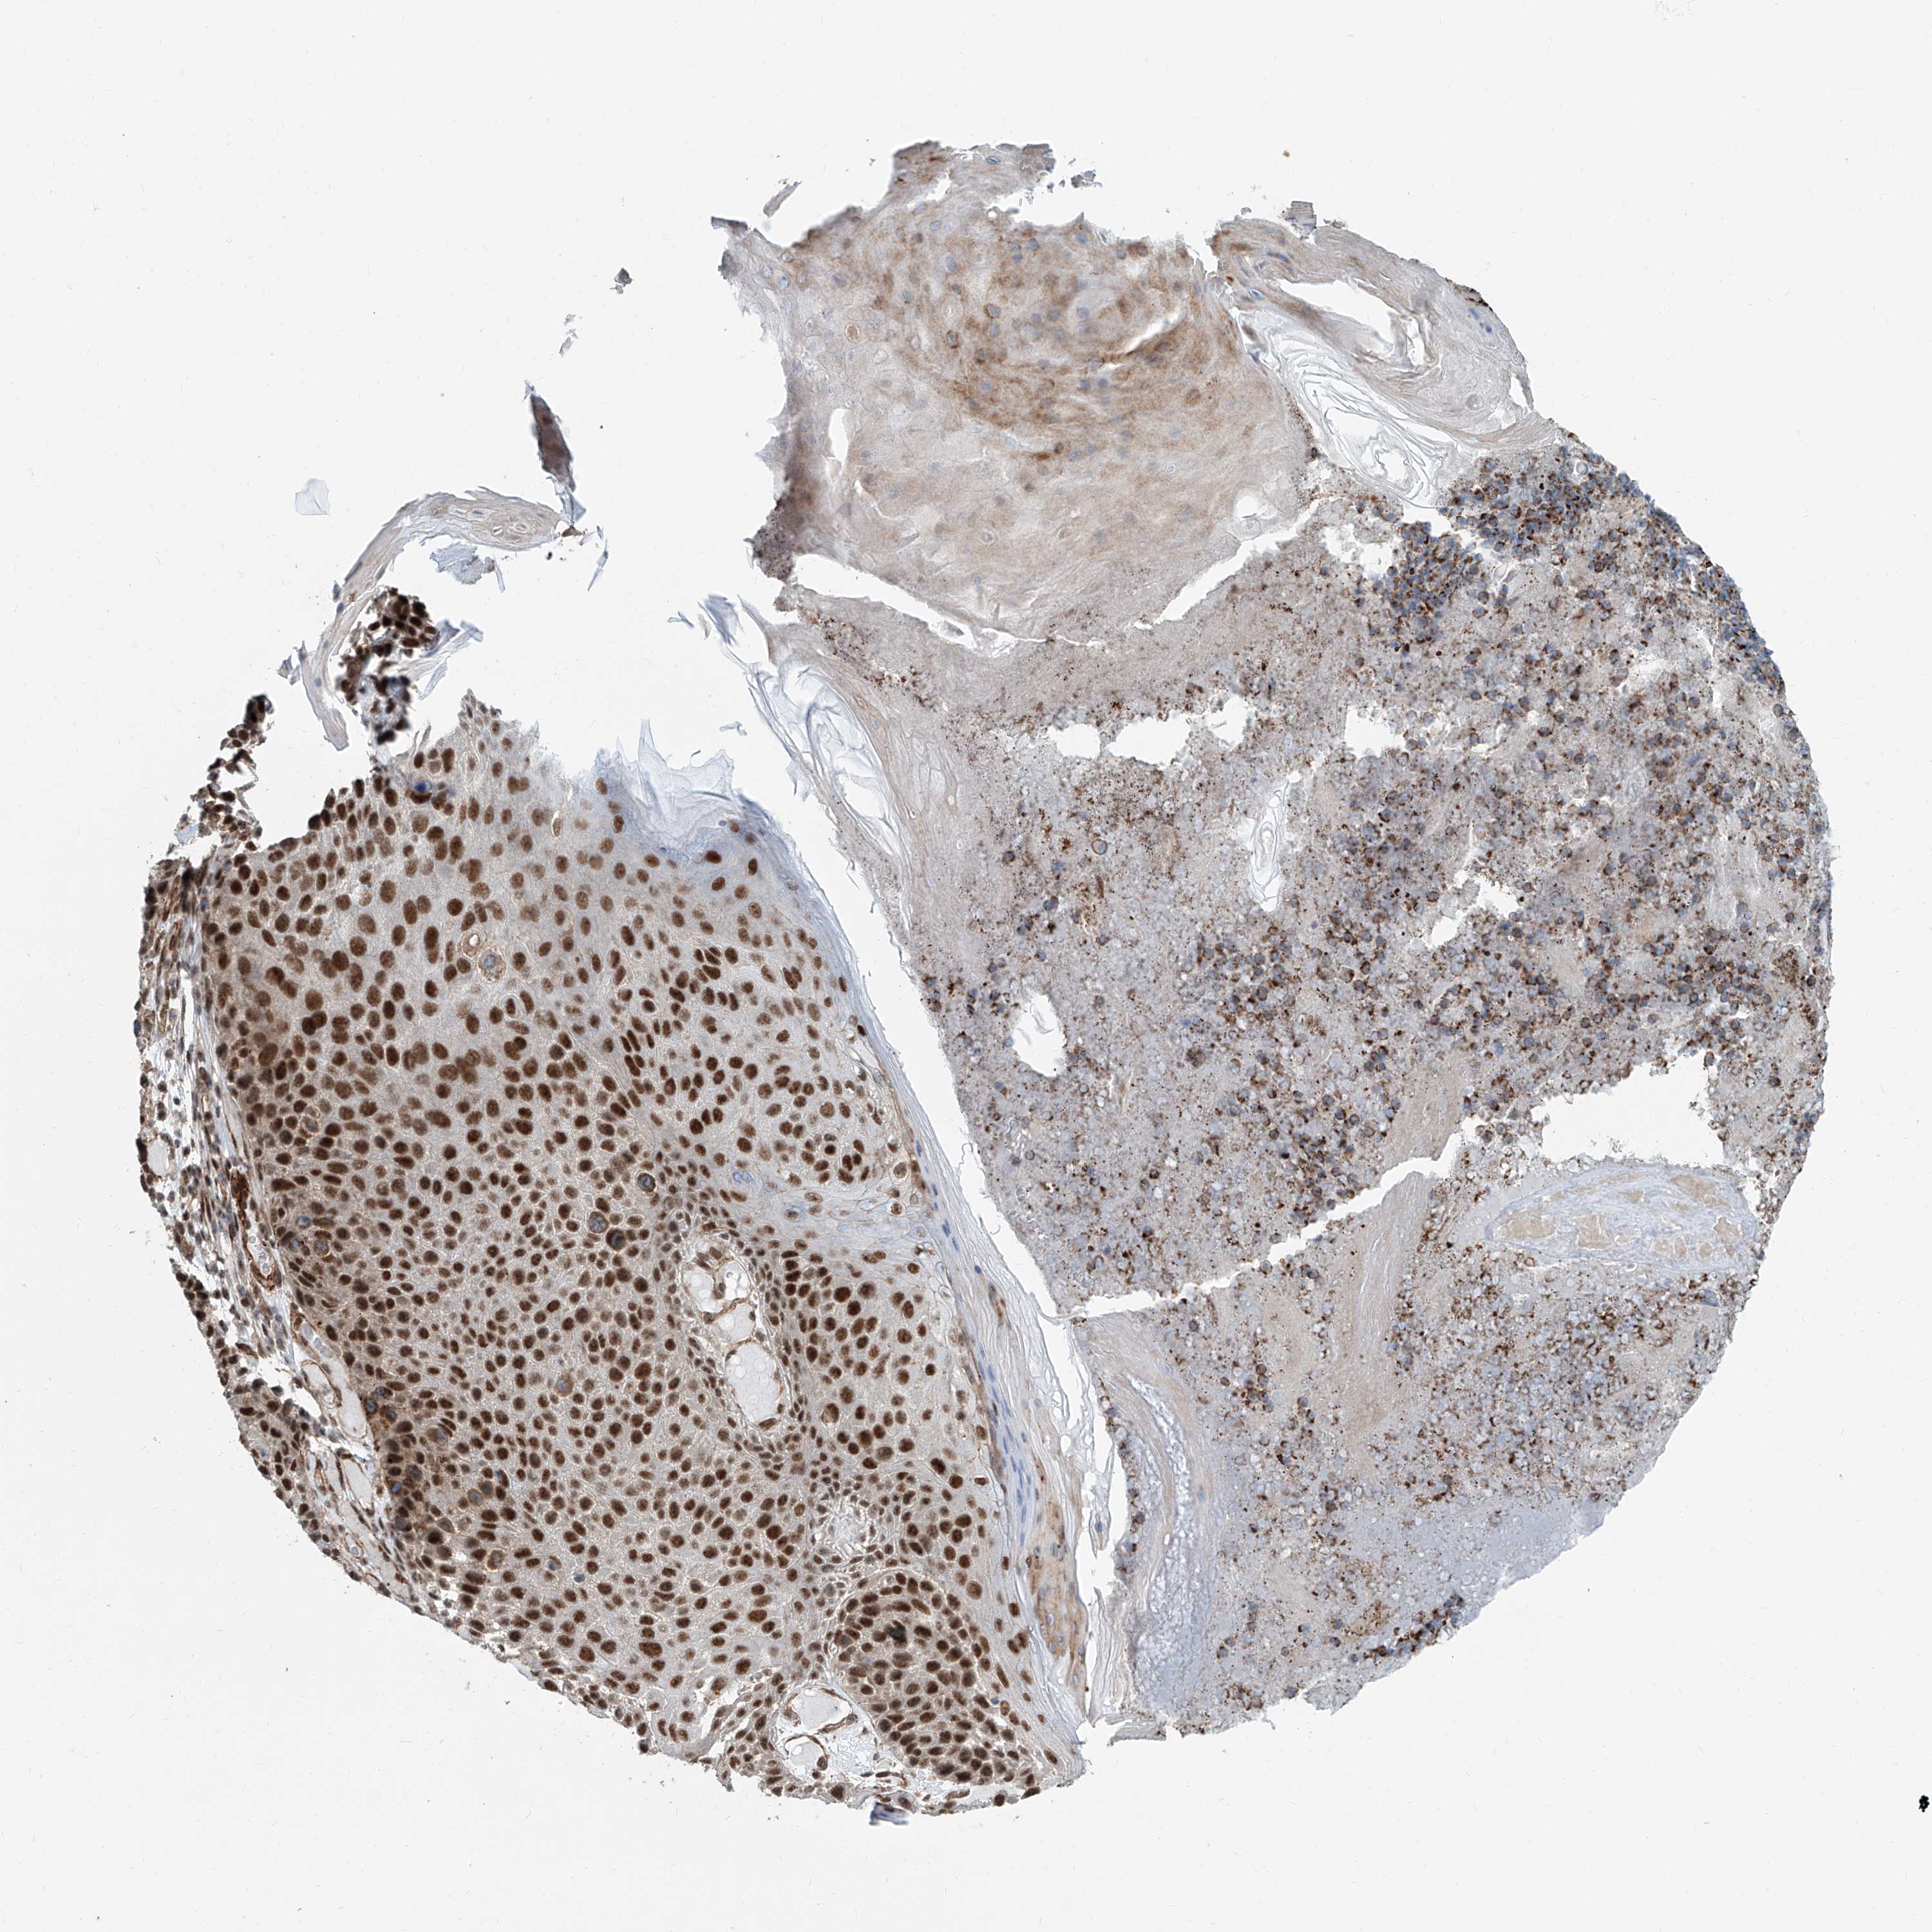

SKIN CANCER - Protein expressioni

A mouse-over function shows sample information and annotation data. Click on an image to view it in a full screen mode. Samples can be filtered based on level of antibody staining by selecting one or several of the following categories: high, medium, low and not detected. The assay and annotation is described here.

Each image is clickable and will lead to virtual microscopy that enables deeper exploration of all samples and also displays staining intensity scores, fraction scores and subcellular localization as well as patient and tissue information for each sample.

Antibody HPA028467

Staining

High

Medium

Low

Not detected

Intensity

Strong

Moderate

Weak

Negative

Quantity

>75%

75%-25%

<25%

None

Location

Nuclear

Cytoplasmic/membranous

Cytoplasmic/membranous,nuclear

Basal cell carcinoma